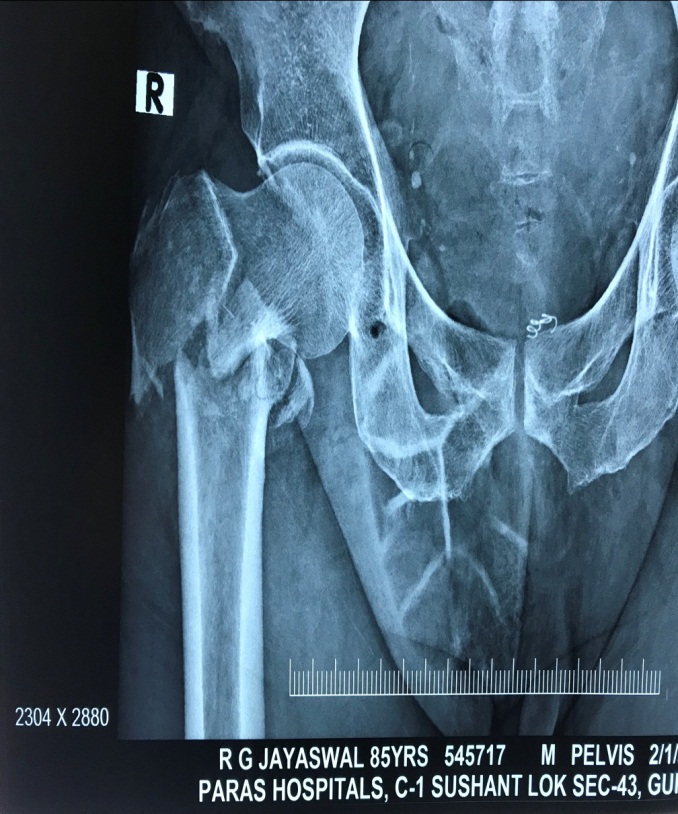

Preop Xray of an osteoporotic hip fracture

osteoporosis